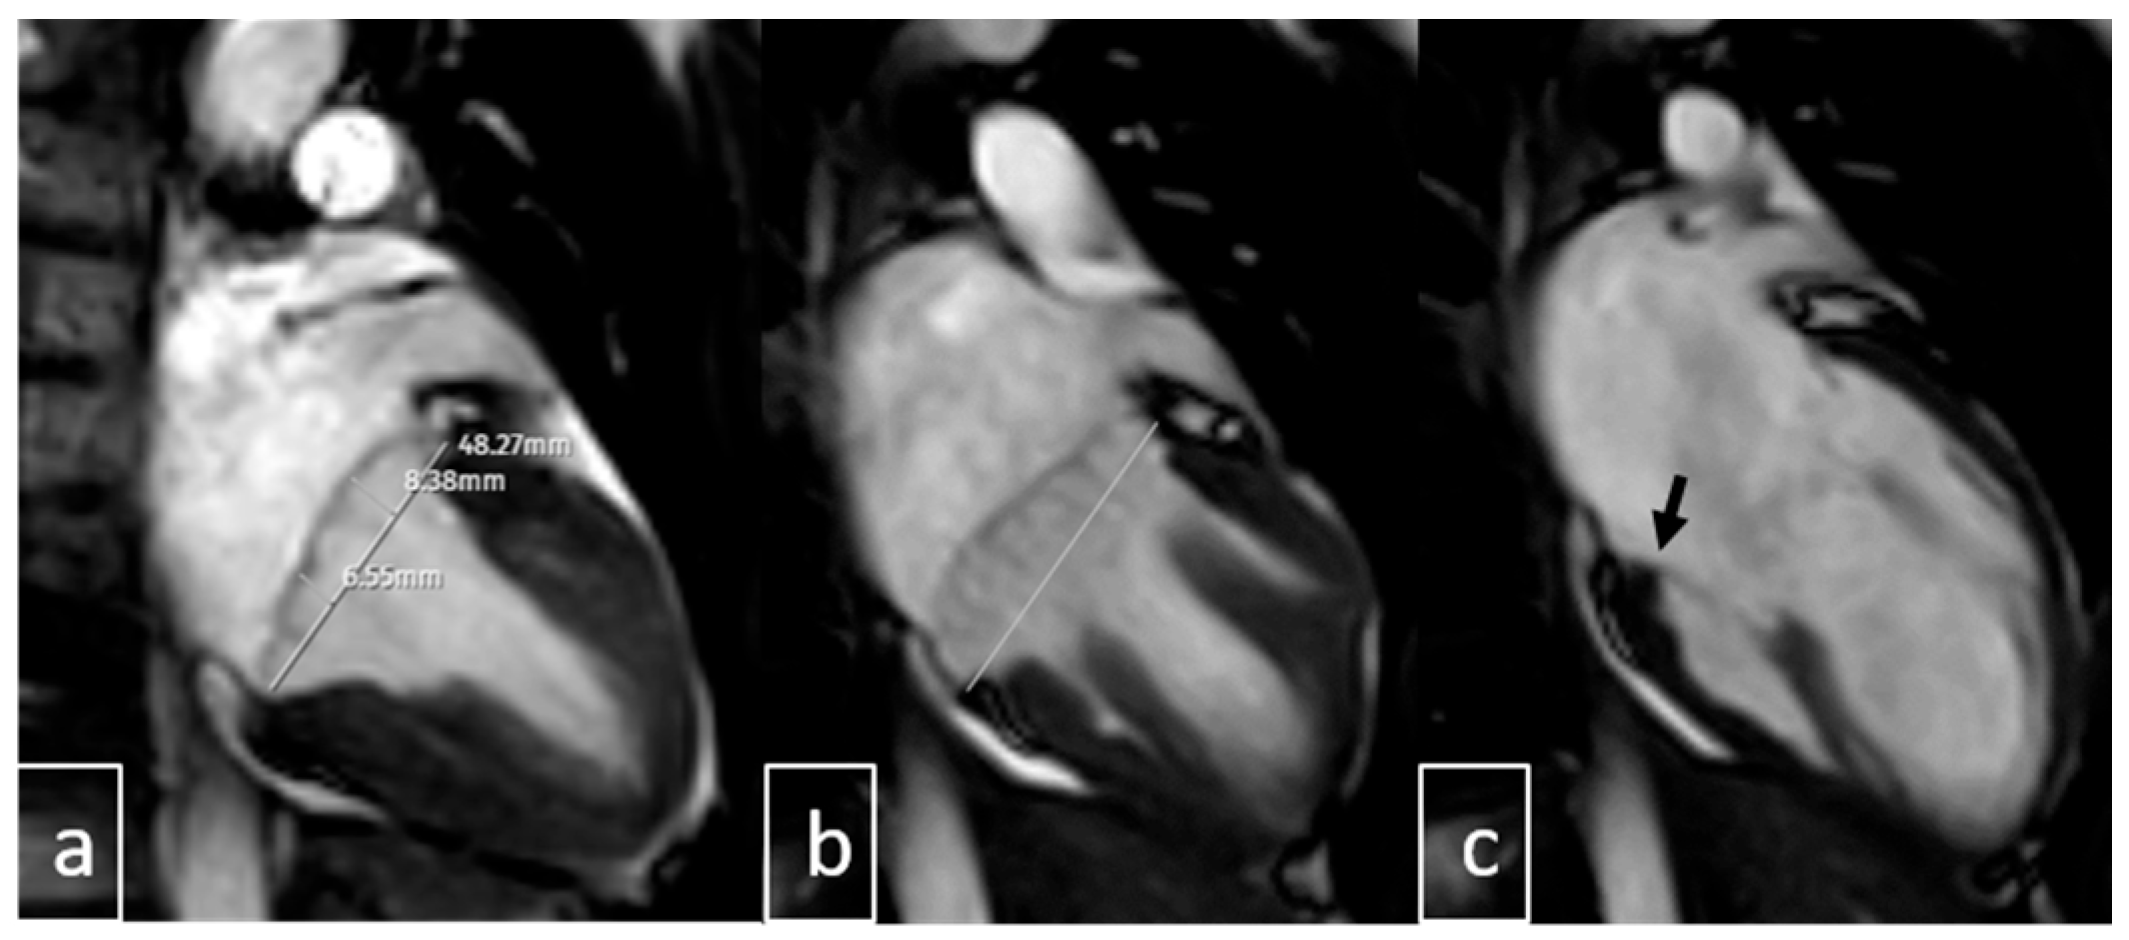

2.4. Image Analysis

3.6. Cardiac MRI Findings in MAD